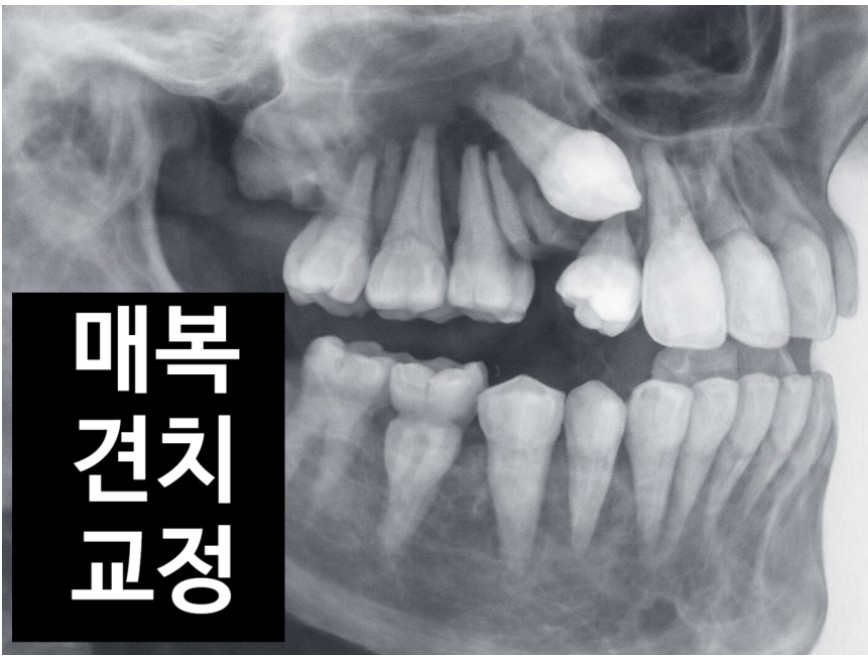

"선생님, 아이 송곳니가 안 나와요. 유치는 빠졌는데 영구치가 없어요!" 어느 날, 이렇게 매복견치(잇몸 안에 묻힌 송곳니) 환자를 만났습니다. 눈에 보이진 않지만, 잇몸 속에서는 이미 다른 치아의 뿌리를 압박하며 조용히 문제를 만들고 있었죠.

왜 송곳니가 매복될까요? 송곳니는 치열 중에서도 가장 늦게 맹출하는 치아입니다. 상악 송곳니의 맹출 시기는 대개 만 11~12세 전후인데, 그때쯤엔 이미 다른 치아들이 자리를 다 차지하고 있습니다. 특히 악궁이 좁은 아이들의 경우, 송곳니가 나올 “길”이 막혀 매복이 생깁니다. 드물게는 과잉치나 치아종, 성장기 외상도 원인이 될 수 있습니다. 통계적으로 약 100명 중 2~3명(2%) 정도에서 매복견치가 발생하며, 그 절반은 다른 치아의 뿌리를 녹이는 치근흡수가 동반됩니다. 이 단계에서 발견이 늦어지면, 인접 치아 손상을 막을 수 없습니다.

‘유치가 빠진 지 6개월이 넘었는데 송곳니가 안 보인다’ — 이 시점이 바로 체크포인트입니다. 이럴 때는 단순 엑스레이보다 CBCT(3차원 영상) 검사가 효과적입니다. CT를 통해 송곳니가 입천장 쪽(구개측)에 숨어 있는지, 입술 쪽(협측)에 가까운지 확인해야 합니다. 위치를 정확히 파악하면 치료 방향이 완전히 달라집니다. 매복이 얕다면 단순히 잇몸을 살짝 열어 교정력으로 끌어내는 ‘노출+견인술’만으로 충분하지만, 깊다면 미니스크류를 이용한 간접 고정원을 함께 써야 합니다.

진단 및 계획 수립 촬영한 CT와 파노라마 이미지를 바탕으로 송곳니의 위치와 각도를 세밀하게 분석합니다. 공간 확보 매복된 송곳니가 들어갈 자리를 먼저 만들어야 하기에, 앞니와 어금니 사이 공간을 코일 스프링으로 벌립니다. 외과적 노출 잇몸을 최소 절개하여 매복된 송곳니 표면에 접근하고, 그 위에 ‘교정 버튼’을 부착합니다. 출혈을 최소화해야 버튼이 안정적으로 붙어 재수술을 막을 수 있습니다. 교정적 견인 시작 버튼에 미세한 힘을 주어 송곳니를 점진적으로 올립니다. 일반적으로 4~6개월 내에 잇몸 위로 치아가 모습을 드러내며, 전체 교정 기간은 평균 1년 6개월 정도 걸립니다. 유착 위험 관리 오랫동안 매복되어 있던 치아는 뼈와 붙는 ‘유착’이 생길 수 있으므로, 견인 속도 조절과 주기적 점검이 매우 중요합니다.